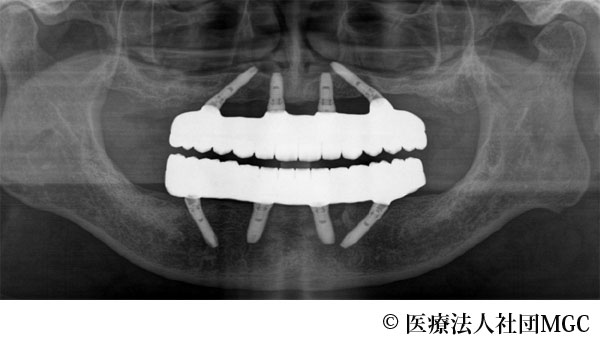

【症例4】上下All-on-4(オールオンフォー)

- 治療前

- 治療後

- 治療名

- 上下All-on-4(オールオンフォー)

- 費用

- 5,888,300円(税込)

- 期間

- 5ヵ月

歯の汚れが気になるのと、奥歯で噛めないとお困りでご来院されました。

ご相談の結果、患者様の生活の質(QOL)を向上させ、しっかり噛め、審美的にも重視した、上下All-on-4(オールオンフォー)を行いました。

機能性、審美性ともに改善し、満足していただけました。